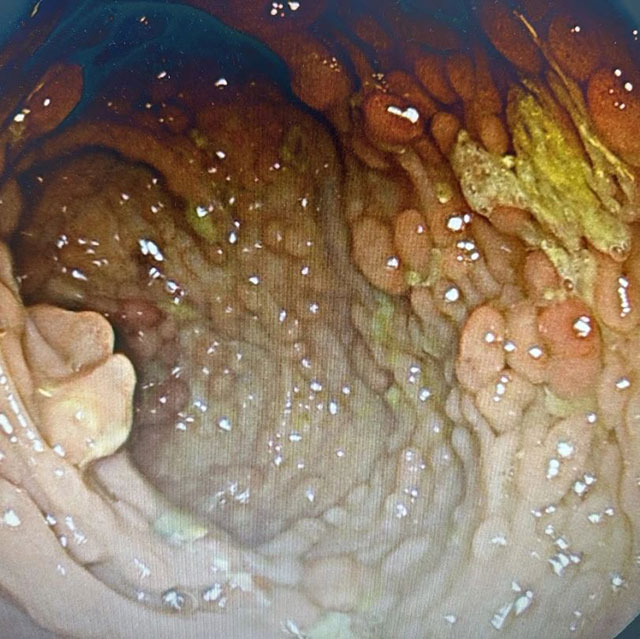

入院后,医生为赵大叔安排了肠镜检查,果真查出了大问题:整个肠壁都是密密麻麻的小息肉,了解了赵大叔的家族史后,医生根据其情况,最终明确诊断为家族性腺瘤性息肉病。最终,医生为其实施了全结肠切除+回肠直肠吻合术。

据肛肠科副主任贾英田介绍,家族性腺瘤性息肉病是一组以结直肠多发腺瘤为特征的常染色体显性遗传的综合征,该病的特征是结肠和直肠内生腺瘤可达数十枚至数千枚,并伴有结肠外表现,常表现为一组疾病群。如果不及时治疗,不可避免地会出现癌变,且可表现为同时多原发性肠癌,属于遗传性大肠癌的一种。

患者的结直肠一般在10~15岁开始出现腺瘤,到25岁时约90%已有腺瘤发生,通常从息肉出现到癌变的平均时间为15年。家族性腺瘤性息肉病平均癌变年龄在39岁(34~43岁),平均死亡年龄40岁。

家族性腺瘤性息肉病的主要症状包括腹痛、腹泻或便频或大便性状改变、便血、贫血、消瘦、发力等。每个患者,甚至在同一个家庭里的患者的临床表现可能不尽相同。至目前为止,手术是治疗家族性腺瘤性息肉病及其癌变的首选方案。